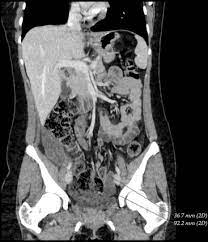

Intra Abdominal Benign Multicystic Peritoneal Mesothelioma Sciencedirect

Intra Abdominal Benign Multicystic Peritoneal Mesothelioma Sciencedirect from ars.els-cdn.com